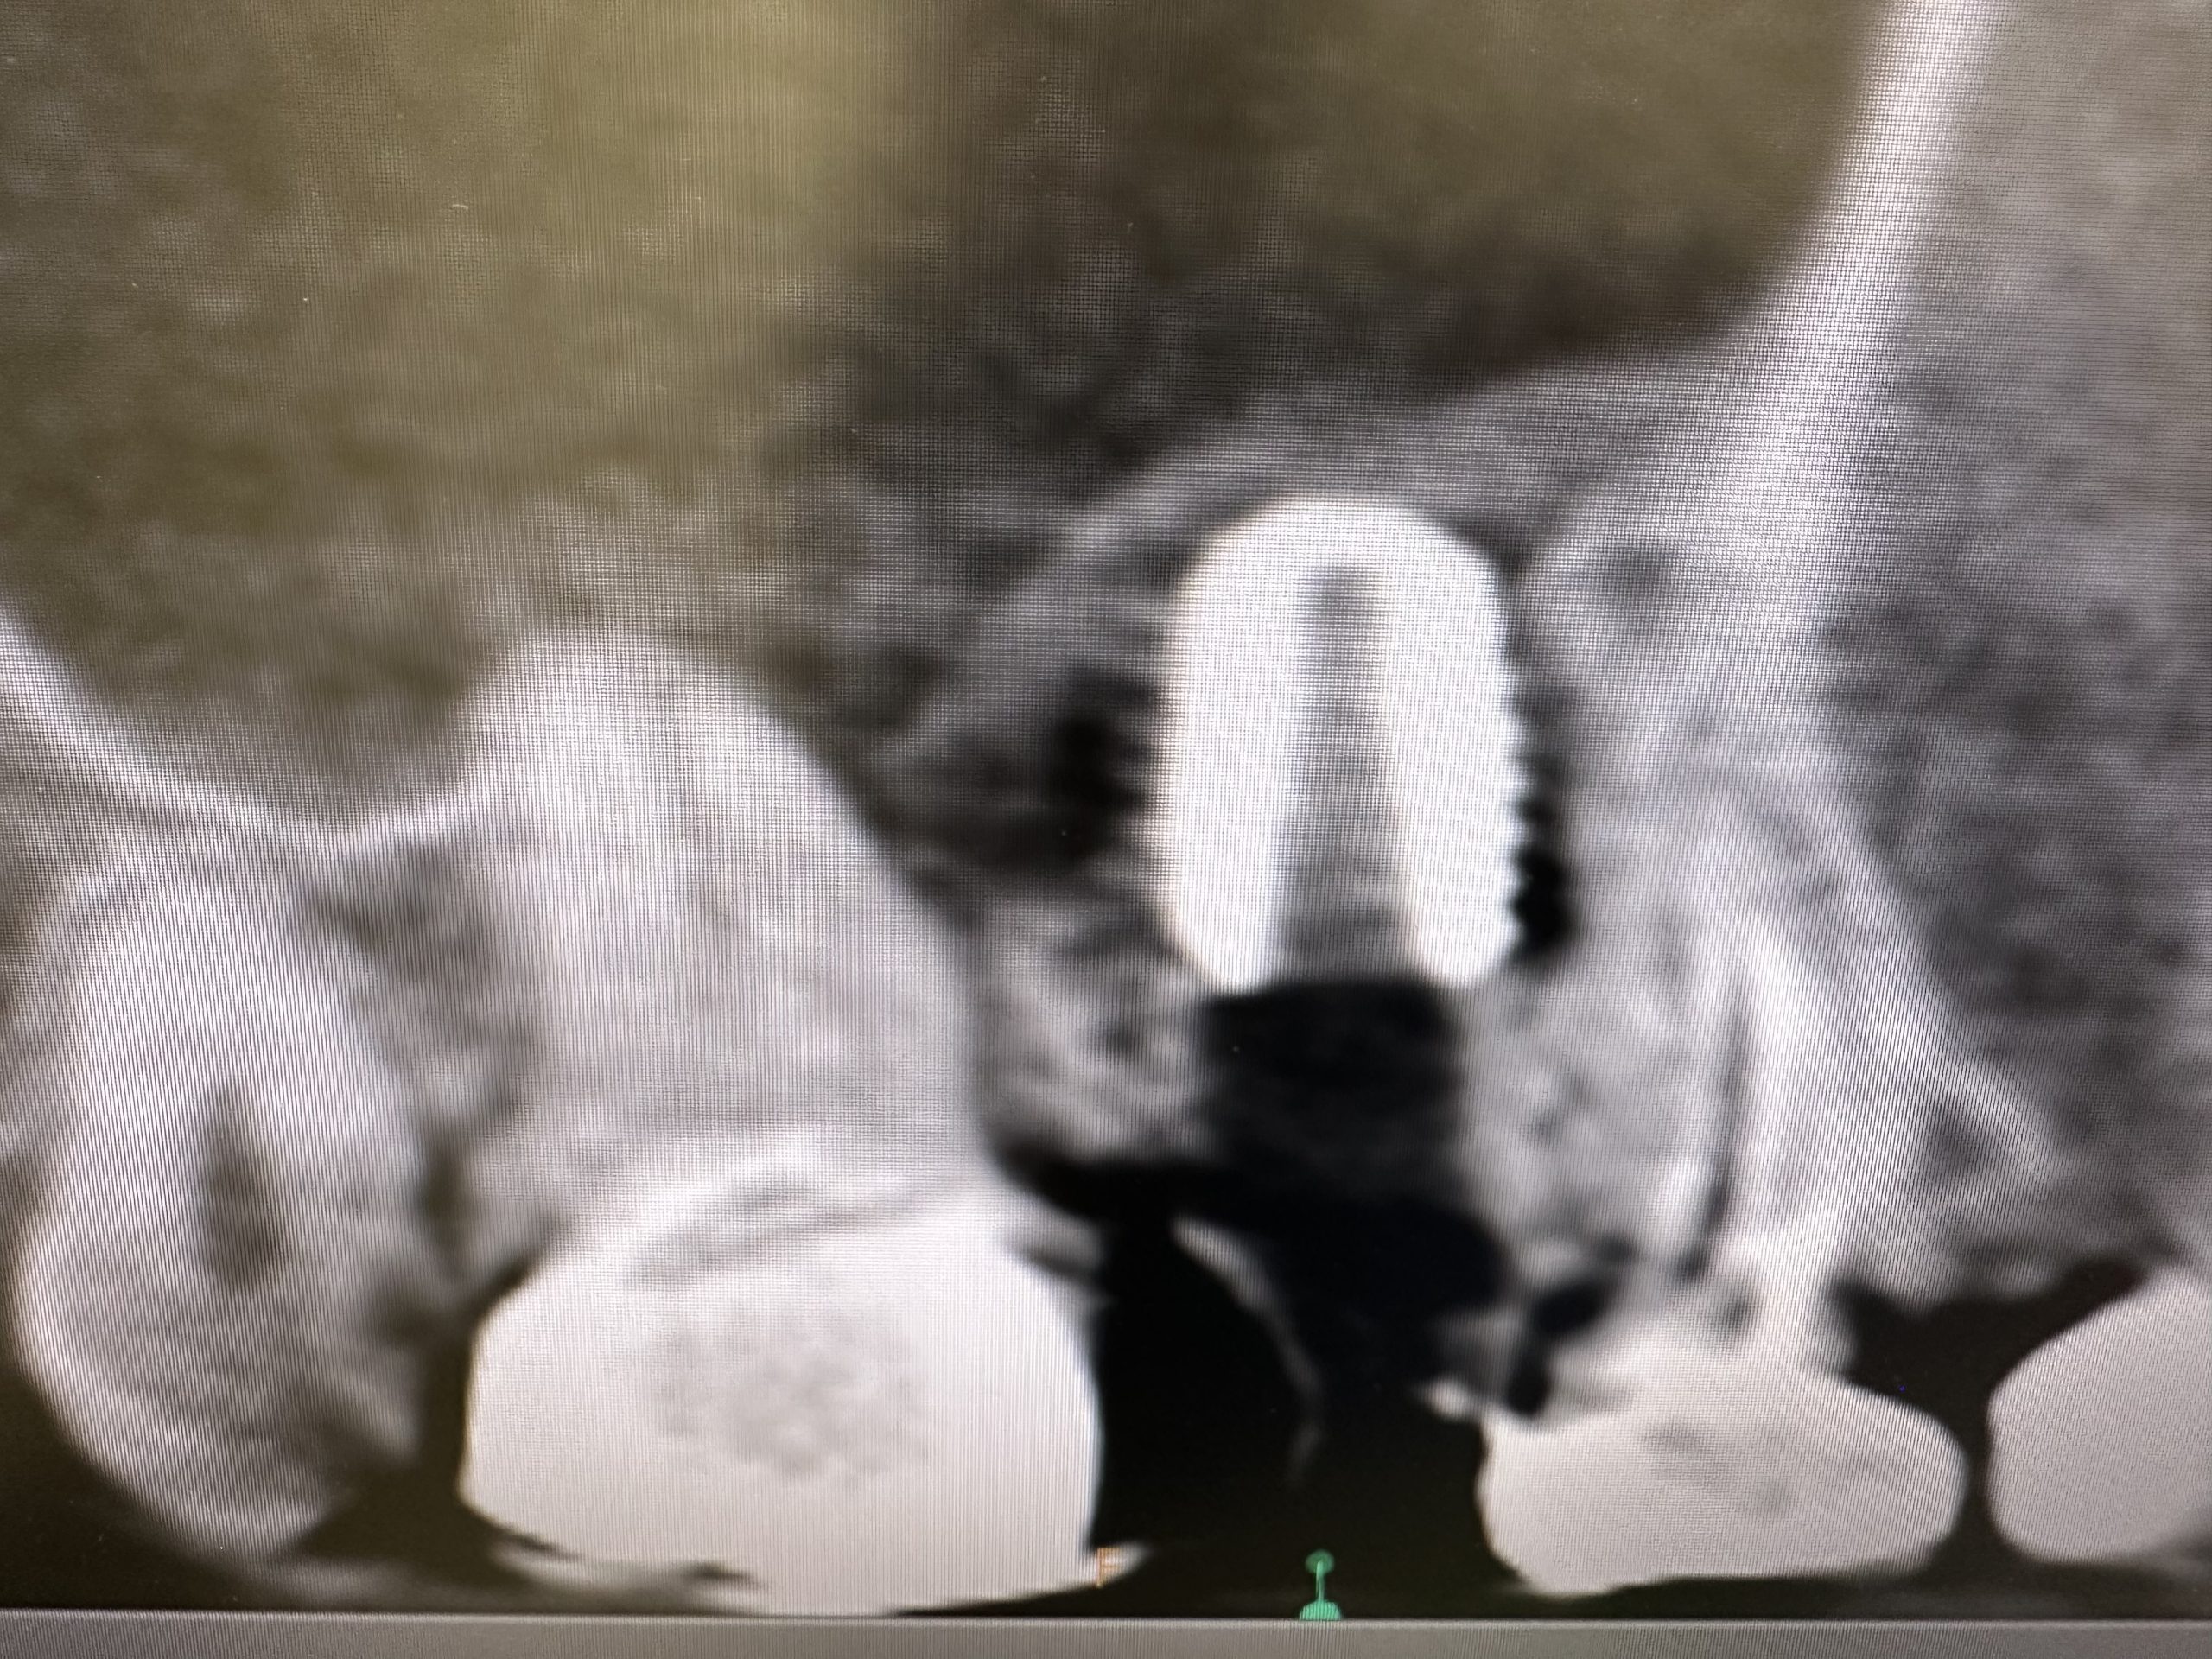

昼からインプラントオペ、ソケットリフト併用

切開から埋入まで20分で終わり💪

毎度同じようなリフト🤪

デンサーリフトは早い、安全!